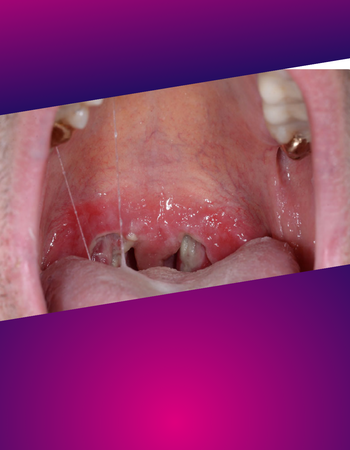

Diagnose-Quiz

Sieht man in der Ferne einen Vogel über die Kieler Bucht fliegen - was ist es wohl? Eine Möwe oder ein Kolibri? Oft liegt die Antwort scheinbar auf der Hand und das fast unmögliche wird gar nicht erst bedacht. So entpuppt sich manch harmloser Pickel erst auf den zweiten oder gar dritten Blick als echter Spezialfall. Andere Symptome sieht man einmal in zehn Jahren und kann sie deshalb evtl. nicht geich zuordnen... Unser Diagnose-Quiz fordert Dich mit ungewöhnlichen oder kniffligen Fällen heraus, die das Hirn so richtig auf Trab bringen.

Die Diagnosequizze werden uns freundlicherweise zur Verfügung gestellt vom "Journal der Deutschen Dermatologischen Gesellschaft" © Deutsche Dermatologische Gesellschaft